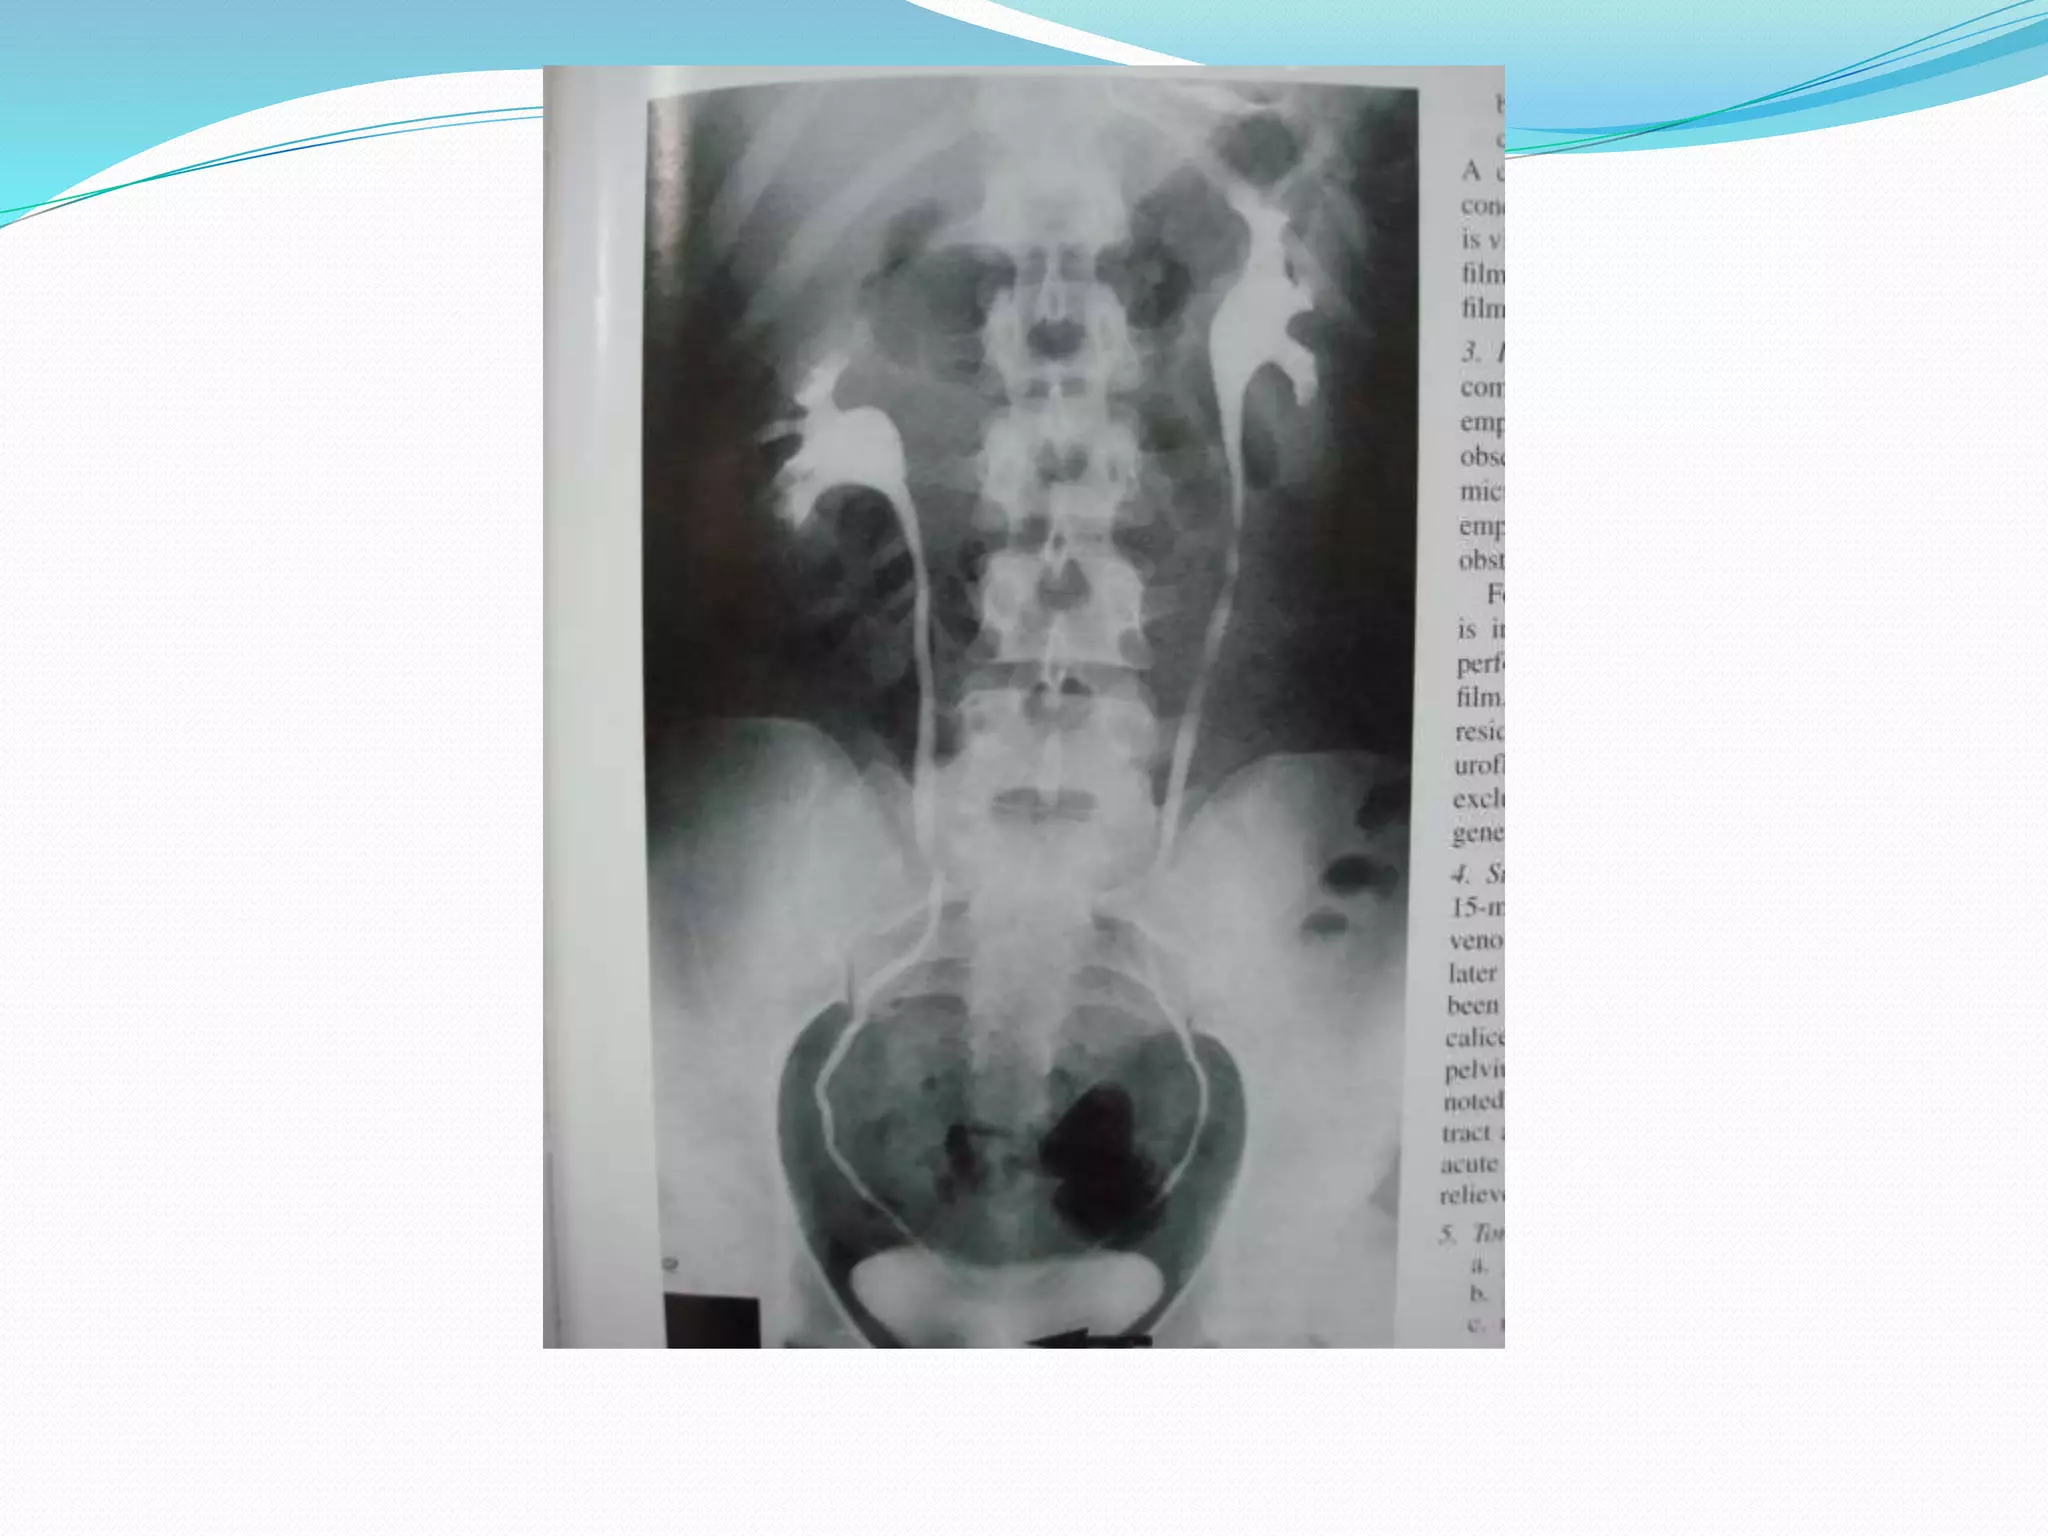

15-min Release film

 Supine AP film

 This film is taken to

show whole urinary

tract.

 After compression is released ,there is transient

increase in flow down the ureters and release film

offers the best chance of demonstrating the

ureters.

 Normal ureters exhibit peristalsis and on a single

film it is uncommon to demonstrate entire length

of both (or even either ) ureters.